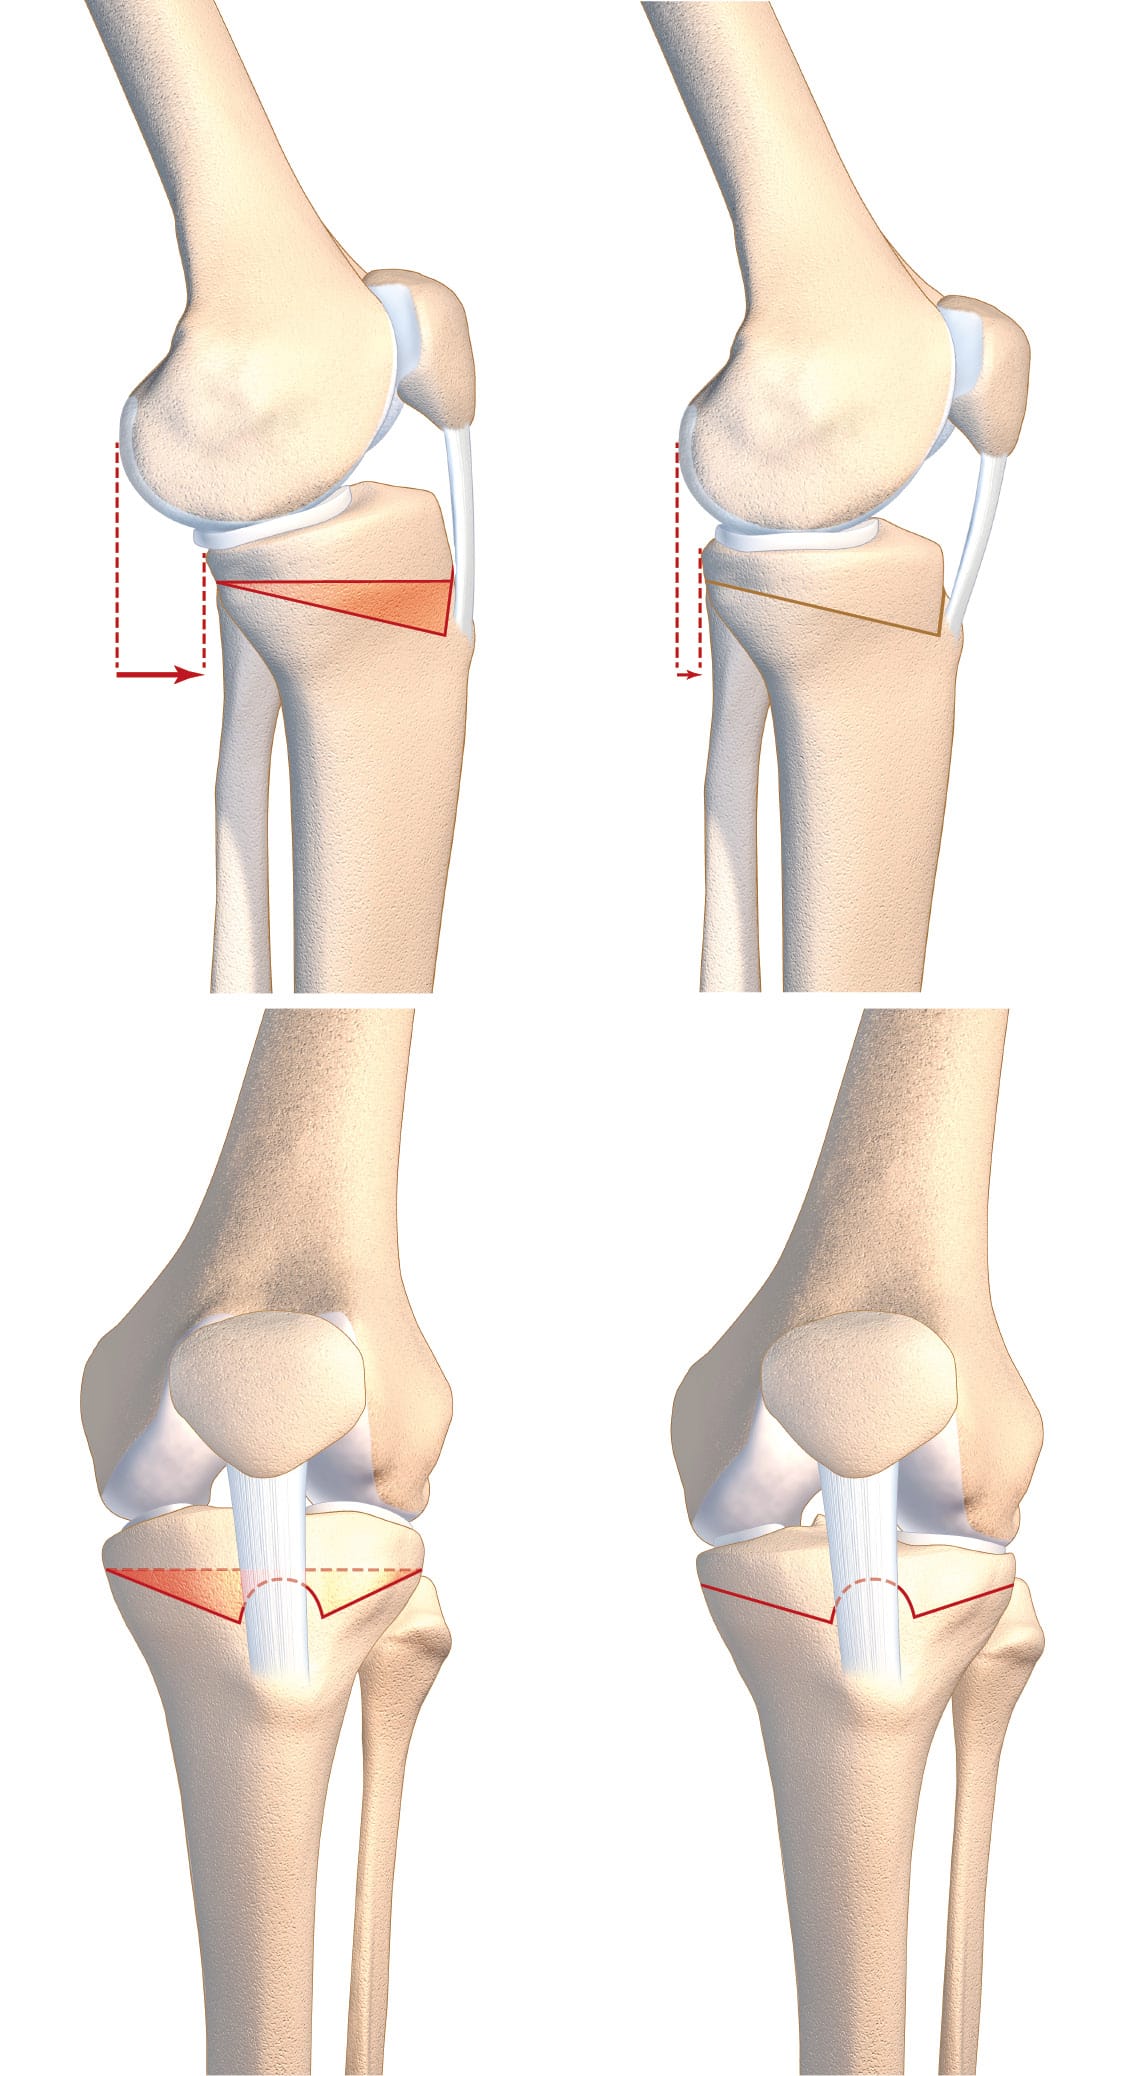

The intervention that directly addresses tibial slope is the tibial deflexion osteotomy (TDO) [18] Guarino A, Pineda T, Giovannetti de Sanctis E, van Rooij F, Saffarini M, Dejour D. The Original Technique for Tibial Deflexion Osteotomy During Revision Anterior Cruciate Ligament Reconstruction: Surgical Technique. Arthroscopy Techniques. 2024 Jan 1;13(1):102824. . This intervention was notably described by Dejour et al. in 1998, although it has been discussed at the Lyon Knee Surgery Congress since the early 1990s [19], Dejour D, Kuhn A, Dejour H. Osteotomie tibiale de déflexion et laxité chronique antérieure à propos de 22 cas. Rev Chir Orthop 1998 ; 84 SII : 28-29 [20] 7èmes journées lyonnaises de chirurgie du genou - Lyon 1991 [Internet]. [cited 2024 Aug 23]. Available from: http://lyon-knee-surgery.com/images/pdf/7%C3%A8mes%20journ%C3%A9es%20lyonnaises%20de%20chirurgie%20du%20genou%20-%20Lyon%201991/jdg-7/assets/basic-html/page-270.html. It is a sagittal realignment osteotomy. The technique described here is a supra-tubercular osteotomy (Figure 4). However, trans-tubercle and infra-tubercle strategies are also possible (Figure 5). This intervention is performed at the same time as the ACL reconstruction.

It was in 1991, that the deflexion osteotomy in humans (then called the extension osteotomy) was presented to the Lyon Knee Surgery Congress [20] 7èmes journées lyonnaises de chirurgie du genou - Lyon 1991 [Internet]. [cited 2024 Aug 23]. Available from: http://lyon-knee-surgery.com/images/pdf/7%C3%A8mes%20journ%C3%A9es%20lyonnaises%20de%20chirurgie%20du%20genou%20-%20Lyon%201991/jdg-7/assets/basic-html/page-270.html. It has been known for many years that there is a link between tibial slope, SATT and ruptured ACL graft [22] Napier RJ, Garcia E, Devitt BM, Feller JA, Webster KE. Increased Radiographic Posterior Tibial Slope Is Associated With Subsequent Injury Following Revision Anterior Cruciate Ligament Reconstruction. Orthopaedic Journal of Sports Medicine. 2019 Nov 1;7(11):232596711987937. . There is a linear relationship between increasing the tibial slope and the force that the ACL needs to bear [23] Bernhardson AS, Aman ZS, Dornan GJ, Kemler BR, Storaci HW, Brady AW, et al. Tibial Slope and Its Effect on Force in Anterior Cruciate Ligament Grafts: Anterior Cruciate Ligament Force Increases Linearly as Posterior Tibial Slope Increases. Am J Sports Med. 2019 Feb;47(2):296–302. . After 20 years of follow-up, adolescents with a tibial slope ≥ 12° had a repeat tear rate of up to 78% when a hamstring had been used for the graft [24] Salmon LJ, Heath E, Akrawi H, Roe JP, Linklater J, Pinczewski LA. 20-Year Outcomes of Anterior Cruciate Ligament Reconstruction With Hamstring Tendon Autograft: The Catastrophic Effect of Age and Posterior Tibial Slope. Am J Sports Med. 2018 Mar 1;46(3):531–43. . The short term risk of repeat tear is doubled when the patellar tendon is used [25] Duerr R, Ormseth B, Adelstein J, Garrone A, DiBartola A, Kaeding C, et al. Elevated Posterior Tibial Slope Is Associated With Anterior Cruciate Ligament Reconstruction Failures: A Systematic Review and Meta-analysis. Arthroscopy. 2023 May 1;39(5):1299-1309.e6. . By contrast, a less steep tibial slope (<6°) drastically reduces the risk of repeat tear [26] Bargagliotti M, Benazzo F, Bellemans J, Truijen J, Pietrobono L, Formagnana M, et al. The Role of the Posterolateral Tibial Slope in the Rotational Instability of the Knee in Patients Affected by a Complete Isolated Anterior Cruciate Ligament Injury: Its Value in the Decision-Making Process during the Anterolateral Ligament Reconstruction. Joints. 2019 Sep;07(03):078–83. . SATT, which is itself related to tibial slope, is an indicator of the load that the graft will have to support in weight-bearing. Excessive stress will result in gradual elongation of the graft, meaning there will be residual laxity and, ultimately, an increased risk of fatigue tear (Figure 7) [25], Duerr R, Ormseth B, Adelstein J, Garrone A, DiBartola A, Kaeding C, et al. Elevated Posterior Tibial Slope Is Associated With Anterior Cruciate Ligament Reconstruction Failures: A Systematic Review and Meta-analysis. Arthroscopy. 2023 May 1;39(5):1299-1309.e6. [27] Ni Q kun, Song G yang, Zhang Z jun, Zheng T, Feng Z, Cao Y wei, et al. Steep Posterior Tibial Slope and Excessive Anterior Tibial Translation Are Predictive Risk Factors of Primary Anterior Cruciate Ligament Reconstruction Failure: A Case-Control Study With Prospectively Collected Data. Am J Sports Med. 2020 Oct;48(12):2954–61. .

The procedure to choose to directly address posterior tibial slope is tibial deflexion osteotomy. It is possible to perform a supra-tubercular, trans-tubercle or infra-tubercle deflexion osteotomy, as described above (Figure 7). The most important factor in choosing a technique is that the surgeon feels at ease using it, since there is currently no technique emerging as superior to any other and each one has its own advantages and drawbacks [29] Onishi S, Kim Y, Nakayama H, Mansour AA, Lowe WR, Ollivier M. Infratubercle Anterior Closing Wedge Osteotomy Corrects Sagittal Alignment without Affecting Coronal Alignment or Patellar Height. Journal of Clinical Medicine. 2024 Jan;13(16):4715. . We have set out the technique for the supra-tubercular osteotomy because this technique means that the resection can be made at the site of the deformity, in the metaphysis, in an area that is favourable to bone healing [30] Demey G, Giovannetti de Sanctis E, Mesnard G, Müller JH, Saffarini M, Dejour DH. Posterior tibial slope correlated with metaphyseal inclination more than metaphyseal height. Knee. 2023 Oct 1;44:262–9. . It has been clearly demonstrated that this osteotomy technique preserves sufficient metaphyseal bone for fixation [31] Demey G, Giovannetti de Sanctis E, Mesnard G, Müller JH, Saffarini M, Dejour DH. Sufficient Metaphyseal Bone for Wedge Removal and Fixation Hardware During Supratuberosity Tibial Deflexion Osteotomy in Knees With Excessive Posterior Tibial Slope. Am J Sports Med. 2023 Jul 1;51(8):2091–7. . The goal of this surgery is to obtain a tibial slope of between 4 and 6°, which means that SATT will be kept between 0 and 5mm without increasing the stresses on the posterior cruciate ligament (Figure 8).